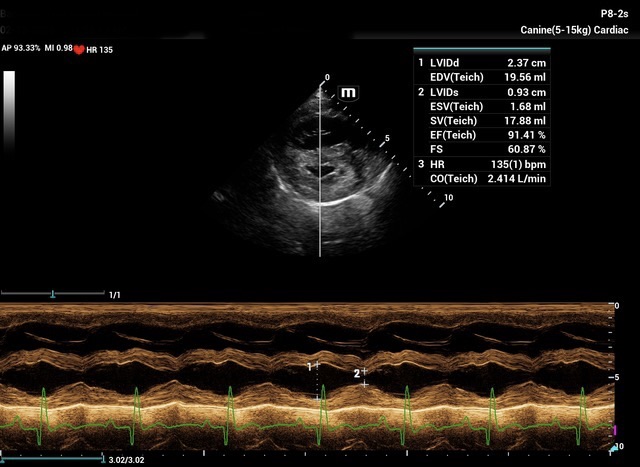

Chronic stage C MVD.TID Pimo and Lasix(high dose), ACEi and Spirono. Doing well. Recheck: Idexx GHP= CBC-NSF ,SDMA 15,BUN 14.1mmol/L, Creat 79umol/L. US: Cornell Indx LVd=1.46(prev2.1), LV septal flattening with diastolic dip,LAAO=2.47,Evel1.45m/s, TVregPG-68mmHg,HV distension-mod ascites.LV and LA underloading via diuretics and PHT (mild PHT past).PHT more pre vs post cap based on small LVsize? Consider Sildenafil/L Arg.Concerned about developing L CHF.Is CHF less likely adding PDE5i with MVD/PHT in underloaded LV than same scenario with vol overloaded LV at similar staging. MVPG=120.3mmHg

My bad! The TV regurge CW Jpeg submitted was mislabeled as MV E vel and its pressure gradient. Sorry for any confucion.

Dan, considering the LAE in addition to LV underloading – does this dog have mitral stenosis?? As you suggested, with this degree of LAE I would expect LVE as well….

Thanks. Not sure if any sig. MV stenosis?? My experience limited.3 PWD from diff times. Ls7 vid. is from 2024,initially thinking reverse remodelling where the lasix lowering preload and Pimo is decreasing LV size via decreased resist/increase cxn while LA no change because it’s a chronic filled remodeled saggy bag receiving Regurge volume??